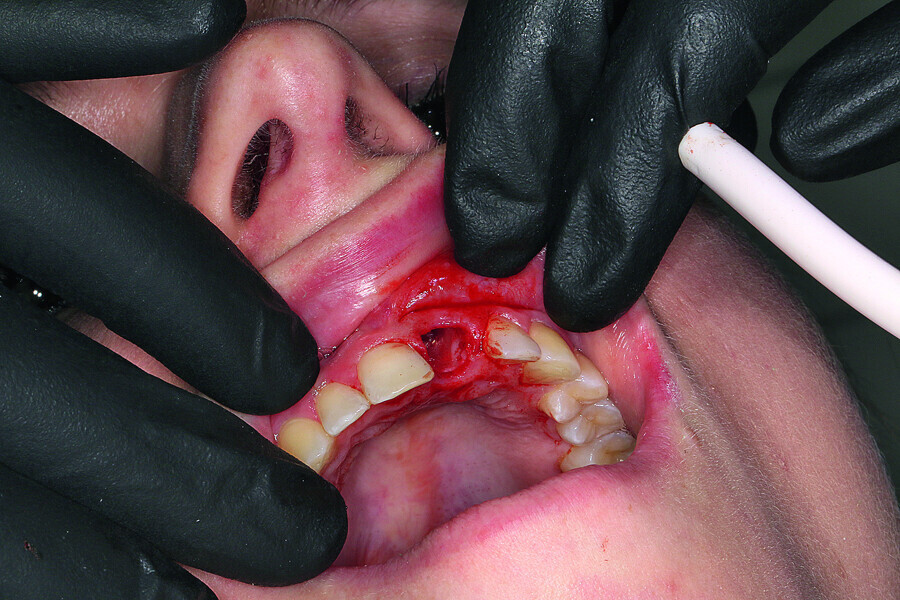

Fig. 7: Gentle extraction preserving the vestibular lamina.